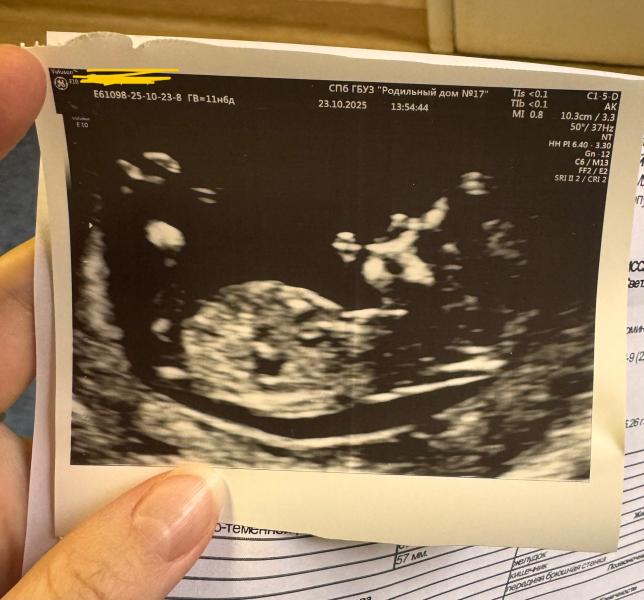

Мальчик или девочка: как определить пол ребенка при беременности

Ну что, погадаем, кто это? Мальчик или девочка?)

Девочка ☺️

Девочка)) вот вот были на узи, такая же картина, прям показывал врач и рассказывал)

Тут мальчик

Мальчик

Девочка 100%

Девочка 👧🏼

Девочка)

Ничего не понятно🙈